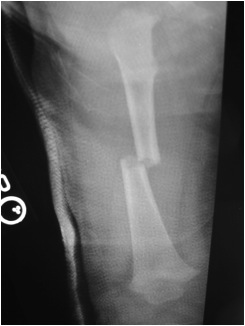

Flexible nails / Titantium Elastic Nails

Indications

- length stable i.e simple transverse, short oblique, midshaft

Technique

Entry points

- medial and lateral insertion

- 1 - 2 cm proximal to distal femoral physis

- oblique entry with awl in direction of nail insertion

- can open with drill bit

- beware proximity of the femoral artery medially

- entry points should be symmetrical

Wire passage

- bend wire for 3 point fixation

- also bend the tip of the wire

- can use F Tool to reduce fracture

- may need small incision and open reduction

- medial entry wire will pass into femoral neck

- lateral entry wire will pass into greater trochanter